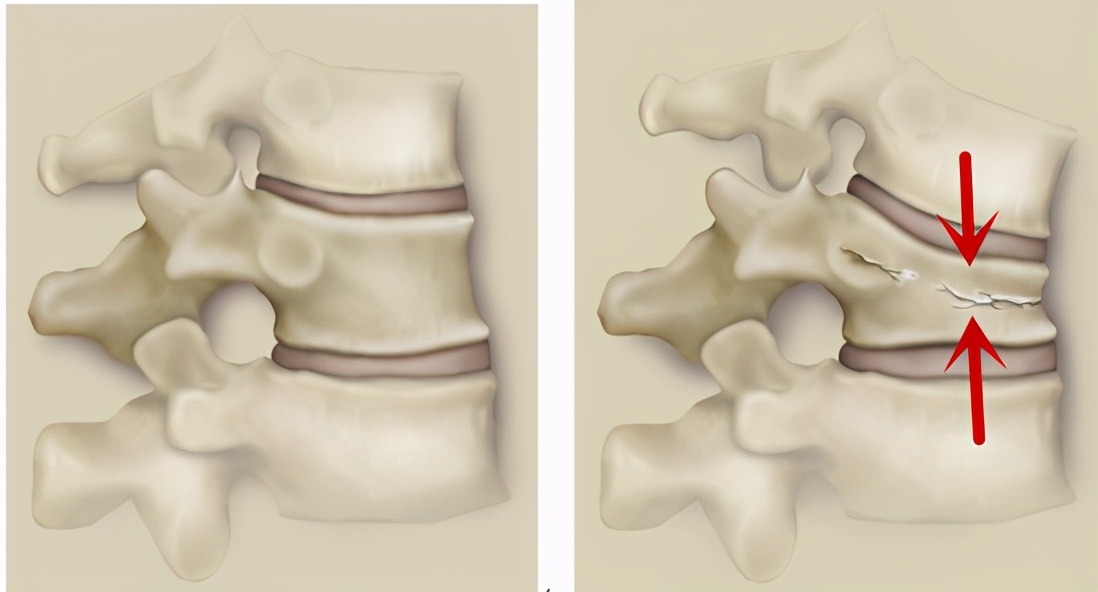

这种骨折是压缩性骨折,如下图,左边所示是正常椎体,而右侧红色箭头就是椎体呈压缩状态。

翻身疼深呼吸疼是怎么回事,向左翻身疼是怎么回事